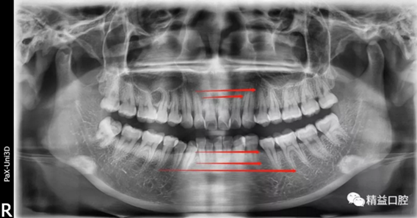

初次看到俊的牙片,我也驚訝到了,畢竟才27歲,上下門牙牙根吸收得非常嚴(yán)重,如果矯正,其中的風(fēng)險(xiǎn)還是非常大的。

矯正前全口曲斷片

從片子上可以清除看到,上牙門牙牙根吸收非常厲害。

李醫(yī)生考慮到俊上下門牙吸收嚴(yán)重,前牙突度大,建議先拔除上頜兩顆四,對上牙進(jìn)行內(nèi)收,后期看矯正效果再對下牙進(jìn)行處理。

為了保證矯正效果和整體牙齒健康,李醫(yī)生在矯正過程中不斷根據(jù)每次牙齒移動(dòng)的情況,對所施加的矯正力以及每次復(fù)診的時(shí)間進(jìn)行精細(xì)的調(diào)整,在放慢矯正速度的同時(shí),以更加輕柔的力量來拉動(dòng)牙齒移動(dòng)。事實(shí)證明一切OK,上牙的內(nèi)收效果非常的好。